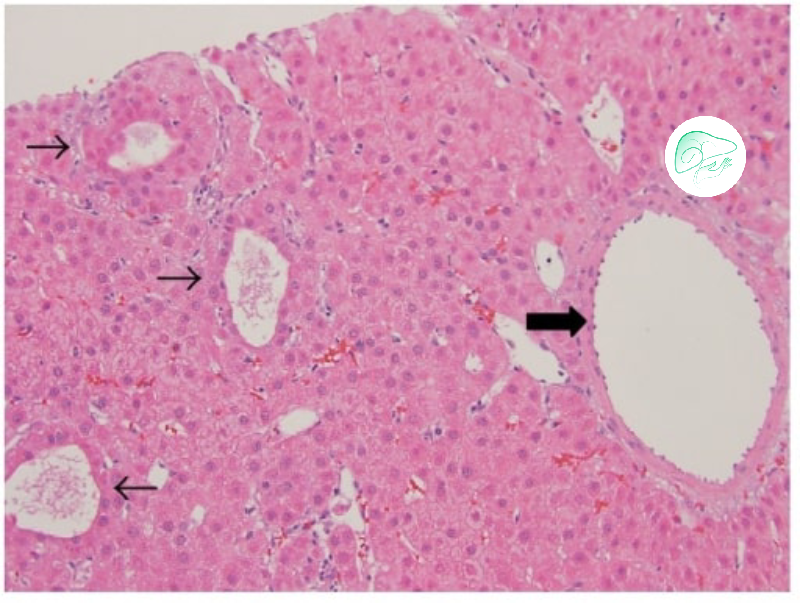

الخزعه (أخذ عینه نسیجیه):

فی بعض الحالات، إذا کانت نتائج الفحوصات التصویریه غیر واضحه، قد یلجأ الطبیب إلى أخذ خزعه من الکبد.

فی هذه الطریقه، تُؤخذ عینه صغیره من نسیج الکتله الکبدیه ویتم فحصها تحت المجهر لتأکید طبیعه الورم.